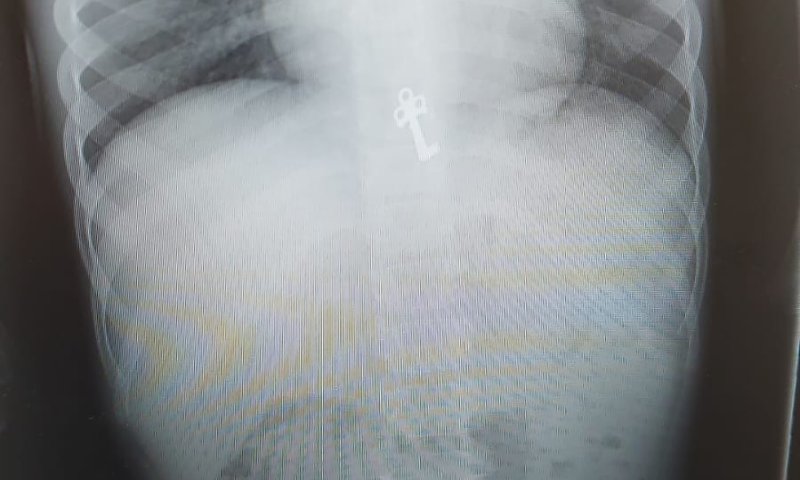

בצילום חזה, מצא רופא הילדים ד"ר חגי שטרן את המפתח הזעיר כשהוא בקיבתו של הילד. היותו של המפתח משונן ודוקרני חייב פעילות פולשנית של הוצאת המפתח מחשש לסיכון ולקרע במעבר למעי, ובשל כך הועבר הילד לחדר ניתוח בבית החולים.